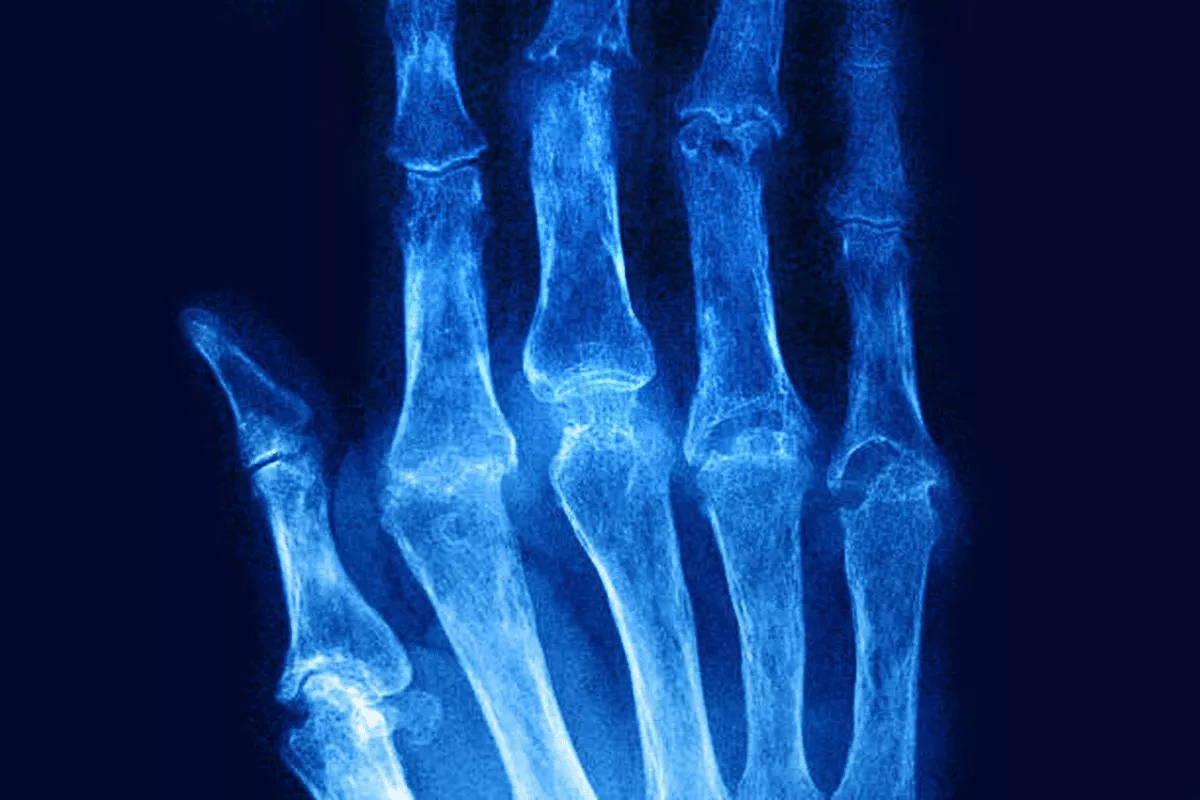

Diagnosing rheumatoid arthritis involves several steps. Your doctor will look at your medical history and perform a physical exam. They might also do blood tests for specific antibodies.

Imaging studies like X-rays or MRI help check for joint damage. This process is vital for finding the right treatment for you.

Significant Joint Inflammation and Cartilage Damage

In Stage 3 RA, joint inflammation gets worse. This leads to a lot of cartilage damage. Such damage can make joints less functional and more painful.

Irreversible Joint Damage and Deformities

Stage 4 RA is marked by severe and lasting joint deformities. The ongoing inflammation and cartilage destruction cause:

- Permanent damage to the joints, leading to loss of function

- Visible deformities that can limit mobility and independence

Irreversible joint damage is a key feature of end-stage RA. It often results in significant disability. Patients may struggle with daily tasks due to lost joint function and mobility.